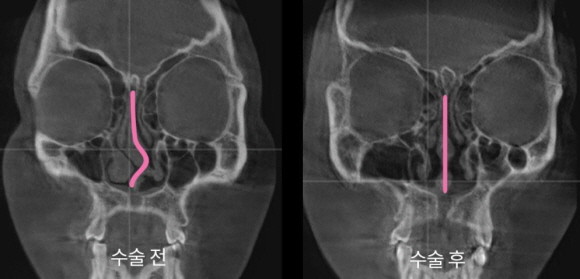

◆아이디병원, 코수술 분야 확장 본격화

아이디병원이 코뼈골절 복원 수술 전문성 고도화 등 코수술 분야 확장을 본격화한다. 병원급 의료기관으로 다양한 전문의 협진 시스템을 갖추고 있는 만큼 전문성을 제고하려는 의도다.

9일 아이디병원에 따르면 아이디병원은 이비인후과, 성형외과, 마취통증의학과 등 전문의 협진 시스템을 이전보다 체계적으로 나눠 세분하고 코의 기능적 부분과 심미성 개선 등 다양한 코 관련 치료를 확대한다.

아이디병원이 코뼈골절 복원 수술 전문성 고도화 등 코수술 분야 확장을 본격화한다. © 아이디병원

그 일환으로 코뼈골절 복원 수술과 관련한 다양한 전문의를 영입하고, 첨단 장비 활용성 확대 등을 통해 수술 전문성을 높였다.

코뼈골절이란 코를 이루고 있는 뼈(비골)의 골절된 상태를 의미한다. 코는 얼굴에서 비교적 약한 부위이면서 돌출된 형태로 외상에 취약하다. 외상으로 코뼈 골절 시 2주가 지나면 코뼈가 골절된 상태로 굳어 5~10일 이내 정확한 진단과 수술을 동반하는 것이 권장된다.

코뼈골절은 모양뿐만 아니라 코라인, 비중격 등 다양한 문제를 유발하며, 개인에 따라 증상도 상이해 각 영역 전문의 간 협진 치료를 기본으로 한다.

아이디병원은 50여명에 달하는 전문 의료진의 정확한 진단과 증상에 따른 협진 시스템을 구축한 만큼 의료 만족도 역시 높아질 것으로 기대하고 있다.